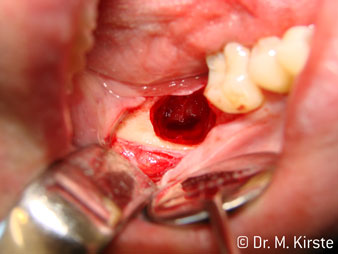

Elegir el ángulo de 45º ofrece múltiples ventajas de uso. Los odontólogos dedicados a cirugía (para quienes se desarrolló principalmente esta pieza de mano) se percatarán de inmediato de que se puede trabajar de forma muy específica. En especial en la remoción de las muelas del juicio (Fig. 2), no es necesaria una gran abducción de las partes blandas en la zona del carrillo (Fig. 3). El diseño del cabezal de la pieza de mano, combinado con los suaves giros del cabezal durante la preparación, permite trabajar de forma rápida y segura en la zona retromolar.

El nuevo diseño de los rodamientos dentro del cabezal de la pieza de mano garantiza el funcionamiento silencioso de la fresa, en la separación del diente o la raíz (Fig. 4-9) se muestra una impresionante imagen de corte sin efectos de impacto.

El contra-ángulo de 45º se adapta muy bien a la mano. Es fácil darse cuenta de que el cabezal de trabajo sigue el ángulo del dedo índice y, así, el movimiento deseado solo se desplaza unos centímetros en paralelo a la punta (Fig. 1)."